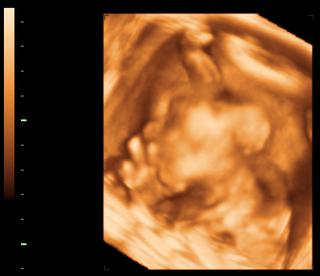

Podle UZ mám pořád dost zvětšené vaječníky a trošku tekutinx v břiše, takže tušíte, diagnostikován mírný hyperstimulační syndrom. 😀 Vzhledem k délce stimulace a množství vajíček je to pochopitelné. Naštěstí je to fakt mírné stádium, transfer bude normálně zítra. Akorát se mám každé ráno vážit a měřit obvod pasu a kdyby čísla stoupala, hned mám přijet. Vzali mi krev, odpoledne mám volat na výsledky. Ale předpokládá se, že to bude už ustupovat, pokud tedy otěhotním, je pravděpodobnost, že by se to mohlo zase trošku zhoršit.. Ale už jsem klidná, vím, co mi je, je mi dobře, tak už jsem vysmátá..ale včera jsem dost vyšilovala.

Ahojky, hlásím největší úrodu, co kdy vůbec byla - 14 vajíček! Tak jsem spokojená, všechny napichnou IMSI, tedy jako ISCI ale nejlepší spermií vybranou co se morfologie týče,takže taky novinka oproti minule. ve středu ráno si mám zavolat, takže věřím,že tentokrate nám zbyde dost i na zamražení. 🙂